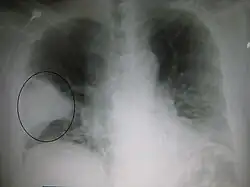

Right upper lobe pneumonia as marked by the circle. -